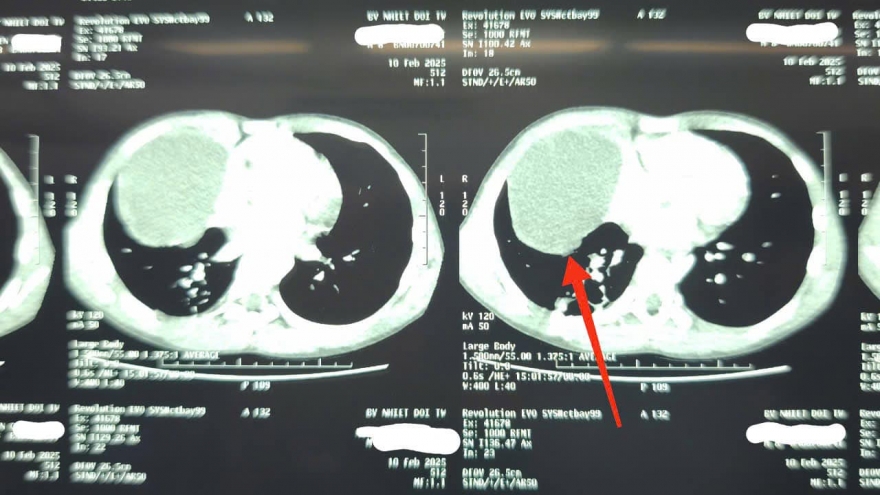

VOV.VN - Việc ứng dụng Kỹ thuật cao trong chẩn đoán, điều trị lao bệnh phổi giúp chẩn đoán nhanh, chính xác, rút ngắn thời gian, giảm chi phí, hỗ trợ điều trị trúng đích, hiệu quả hơn và tăng khả năng kiểm soát dịch bệnh.